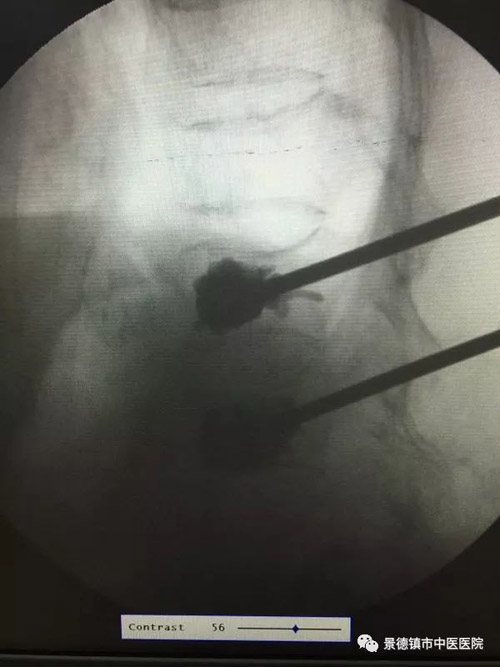

上圖為手術中患者的影像學資料

患者入手術室后開放靜脈輸液,建立有創(chuàng)動脈血壓實時監(jiān)測,常規(guī)心電監(jiān)護,呼末體溫監(jiān)測。為避免插管應激時血流動力波動過大,適時加深麻醉誘導后,順利置入6.5號氣管導管。術中患者生命體征平穩(wěn),并保暖護眼、間斷血氣分析,將患者狀態(tài)調整至最佳。在手術結束后15分鐘患者自主呼吸恢復,應答自如,潮氣量滿意后帶管送入ICU繼續(xù)觀察。續(xù)觀3日后患者康復出院,回訪患者恢復良好。